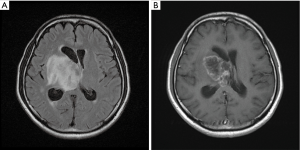

MRI which has been done one month after radiotherapy showed decreased tumor size (28.6 mm × 18.5 mm) as compared to prior MRI (53 mm × 46 mm). Focal cystic change with marginal contrast enhancement was noted within the tumor (Figure 5). However, tumor regrowth was noted 5 months later in follow-up MRI (Figure 6). The regrowth of the tumor was observed from the same location, which was within the GTV field. We considered it a residual tumor with progression. Several episodes of headache and unsteady gait have been noted due to IICP and controlled by medication during the follow-up period. The patient lost to follow-up 6 months after the treatment. The patient developed high fever with urosepsis and visited our emergency department 10 months after the radiotherapy. His condition deteriorated rapidly and expired due to multi-organ failure.